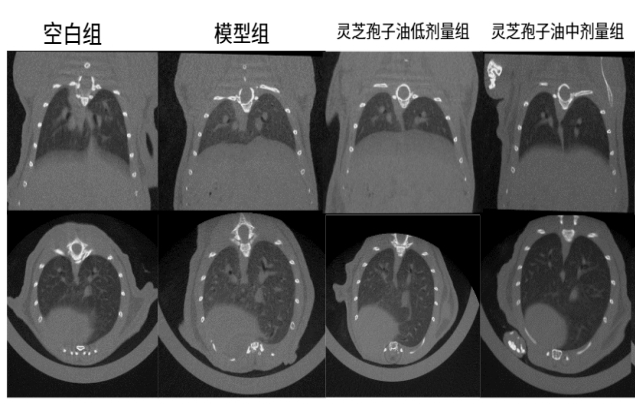

體內(nèi)功效實(shí)驗(yàn)研究結(jié)果表明:在為期52天的小鼠實(shí)驗(yàn)中,每日6粒廣藥牌靈芝孢子油,靈芝孢子油顯著減少了肺部肉芽腫結(jié)節(jié)的面積(減少23.07%)和磨玻璃陰影,降低炎癥因子和趨化因子水平 ,證實(shí)廣藥牌靈芝孢子油具有一定的防治小鼠肉芽腫型肺結(jié)節(jié)的作用。

圖:靈芝孢子油對(duì)肉芽腫型肺結(jié)節(jié)小鼠肺部斷層掃描檢測(cè)結(jié)果及統(tǒng)計(jì)

體內(nèi)作用機(jī)制研究證實(shí):通過(guò)調(diào)節(jié)PI3K-Akt-mTOR信號(hào)通路、抑制p-AKT和p-mTOR活化、糾正代謝紊亂、減少炎癥因子和趨化因子的釋放,最終達(dá)到緩解肉芽腫型肺結(jié)節(jié)的效果。